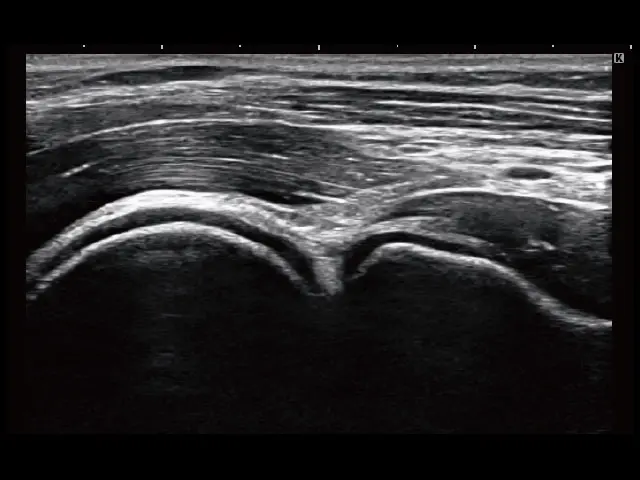

2画面表示(上下/左右)

浅部を多用する運動器診断をストレスなく行うため、上下2画面表示を搭載。左右表示が必要な場合もワンタッチ操作で切り替えが可能です。

イメージギャラリー

イメージ画像を表示する